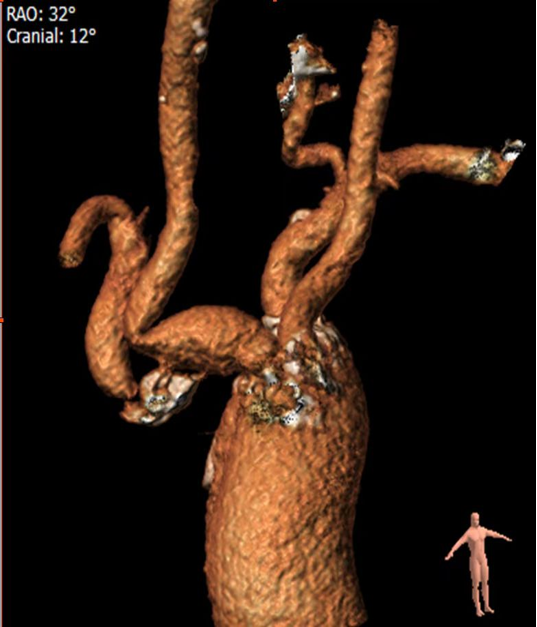

病例二

复杂的右锁骨下动脉闭塞病变:

对于闭塞病变,开通导丝的方向至关重要。根据CTA提示的特定角度(如 RAO 32° CRA 12°)进行投照,能为术者提供最清晰的路径导向,成功引导导丝通过闭塞段。

图:CTA提示 RAO 32  CRA 12

图:按RAO 32  CRA 12开通成功